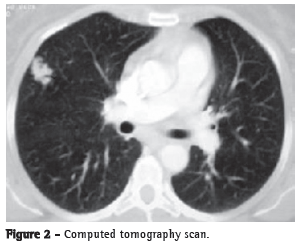

A 57-year-old Caucasian female (born in the city of Juiz de Fora, in the state of Minas Gerais, married, and a retired teacher) was referred to the SPCT-HMS-JF because the X-ray (Figure 1) prior to cholecystectomy revealed a nodule (of unknown stability and with irregular borders) in the right pleural cavity. The patient, who was totally asymptomatic, was a smoker (20 pack-years) and had a family history of cutaneous amyloidosis.

The present case was one of nodular pulmonary amyloidosis, which happened to be diagnosed through tests performed prior to cholecystectomy. The clinical and radiological evidence indicated a nodule of neoplastic origin since the radiological finding revealed a nodule with irregular borders, and the patient had a history of smoking. Consequently, we chose to perform an exploratory thoracotomy that allowed the correct diagnosis, and that, in case of malignancy, would make it possible to perform a potentially curative procedure. Therefore, the X-ray finding of a nodule with irregular borders in the right pleural cavity can lead to the inclusion of pulmonary amyloidosis in the radiological differential diagnosis.